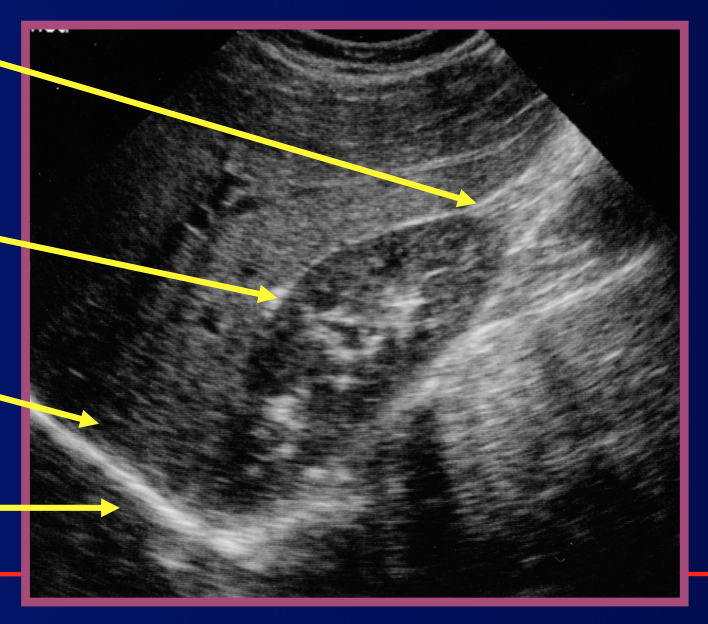

Where is this.

Label it/

RUQ